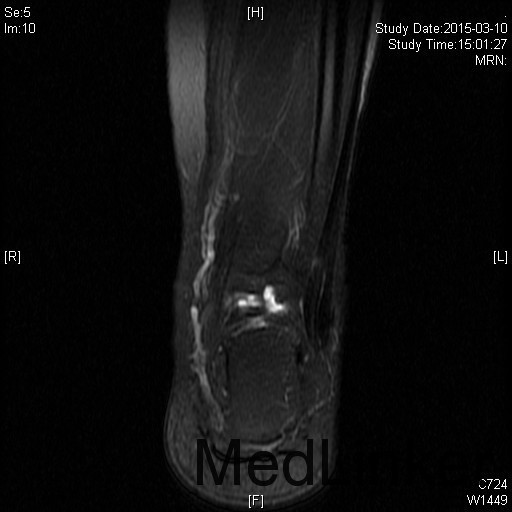

左踝扭伤后肿胀疼痛伴活动受限半年

查体:左腓肠肌萎缩,左踝轻度肿胀。左踝关节ROM较对侧降低,以背伸活动受限最明显。距腓前韧带处未及明显压痛。左踝内、外侧关节间隙压痛(+)。ADT(-),外侧应力试验(-)。左下肢肌张力正常、感觉正常。 辅检:MRI示“左踝关节积液”

诊断:左踝关节创伤性滑膜炎 治疗:左踝关节镜下滑膜清理、胫骨前缘成形

随访:患者术后即刻踝关节活动度恢复正常,2周恢复正常行走。 讨论:踝关节扭伤很常见,扭伤后会发生各种各样的情况。此患者扭伤后继发了滑膜炎,并伤及了关节软骨。这种情况应进行关节镜手术治疗。此外,核磁共振对关节疾患的诊断也是有限的,关节镜才是黄金标准。